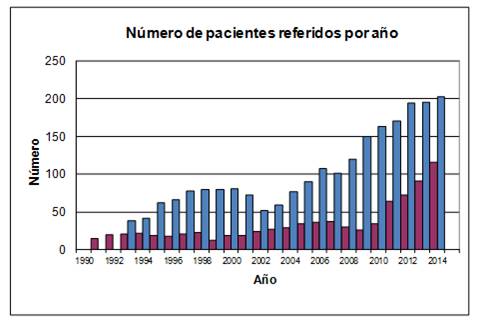

La frecuencia con que fueron referidos los pacientes mostró un aumento persistente en el período 1991 a 2014. La realización de polisomnografías, pasó de 20 a 346 por año, sin diferencias entre el crecimiento en Hospital de Clínicas y el sistema mutual (Figura 1).

Figura 1: Número de pacientes referidos por año. Barra de color oscuro: número de pacientes referidos al Hospital de Clínicas. Barra de color claro: número de pacientes referidos al sistema mutual.

Se apreció una frecuencia mayor de los pacientes del sexo masculino en la práctica mutual (71,9%), con respecto al Hospital de Clínicas (42.8%). La media de edad en el momento de la consulta fue de 52,7 ± 13,5 (rango 5 a 92), con un máximo en la década de 51 a 60 años, y una distribución homogénea en las otras décadas.

La frecuencia de jóvenes referidos por apneas del sueño se revisó retrospectivamente en el período 1998-2014, en el que fue posible calcular la proporción de pacientes menores de 30 años. De 1676 pacientes del sistema mutual, 139 de ellos tenían menos de 30 años. Esta proporción en 1998 correspondió a 4,8% por año, mientras que en 2014 aumentó a 9,1% (Figura 2).

Figura 2: Proporción de pacientes menores de 30 años referidos por apneas del sueño, según año de la consulta. Se observa un incremento sostenido en la última década.